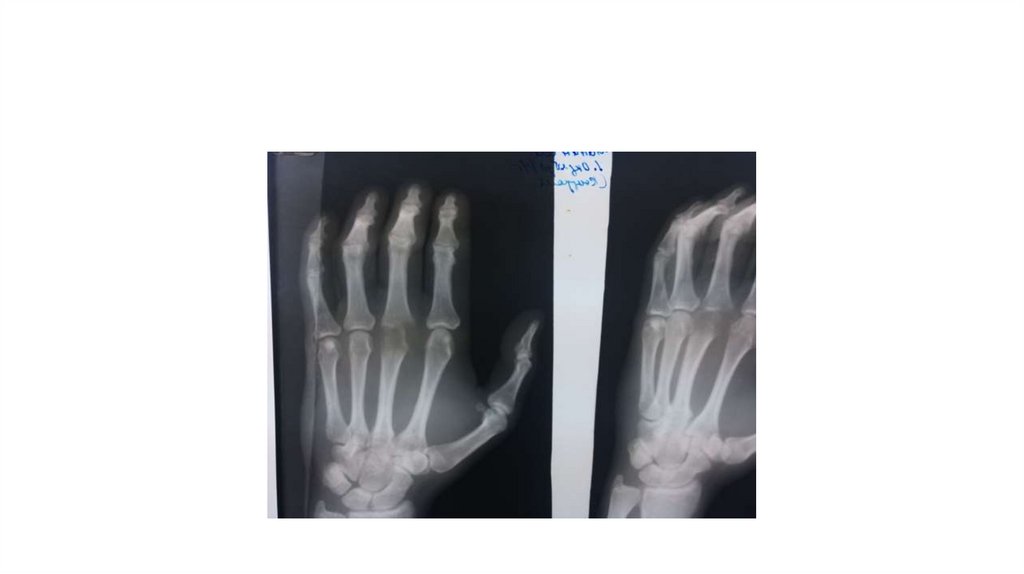

Воспалительные заболевания опорнодвигательного аппарата

«Воспалительные

заболевания опорнодвигательного аппарата»